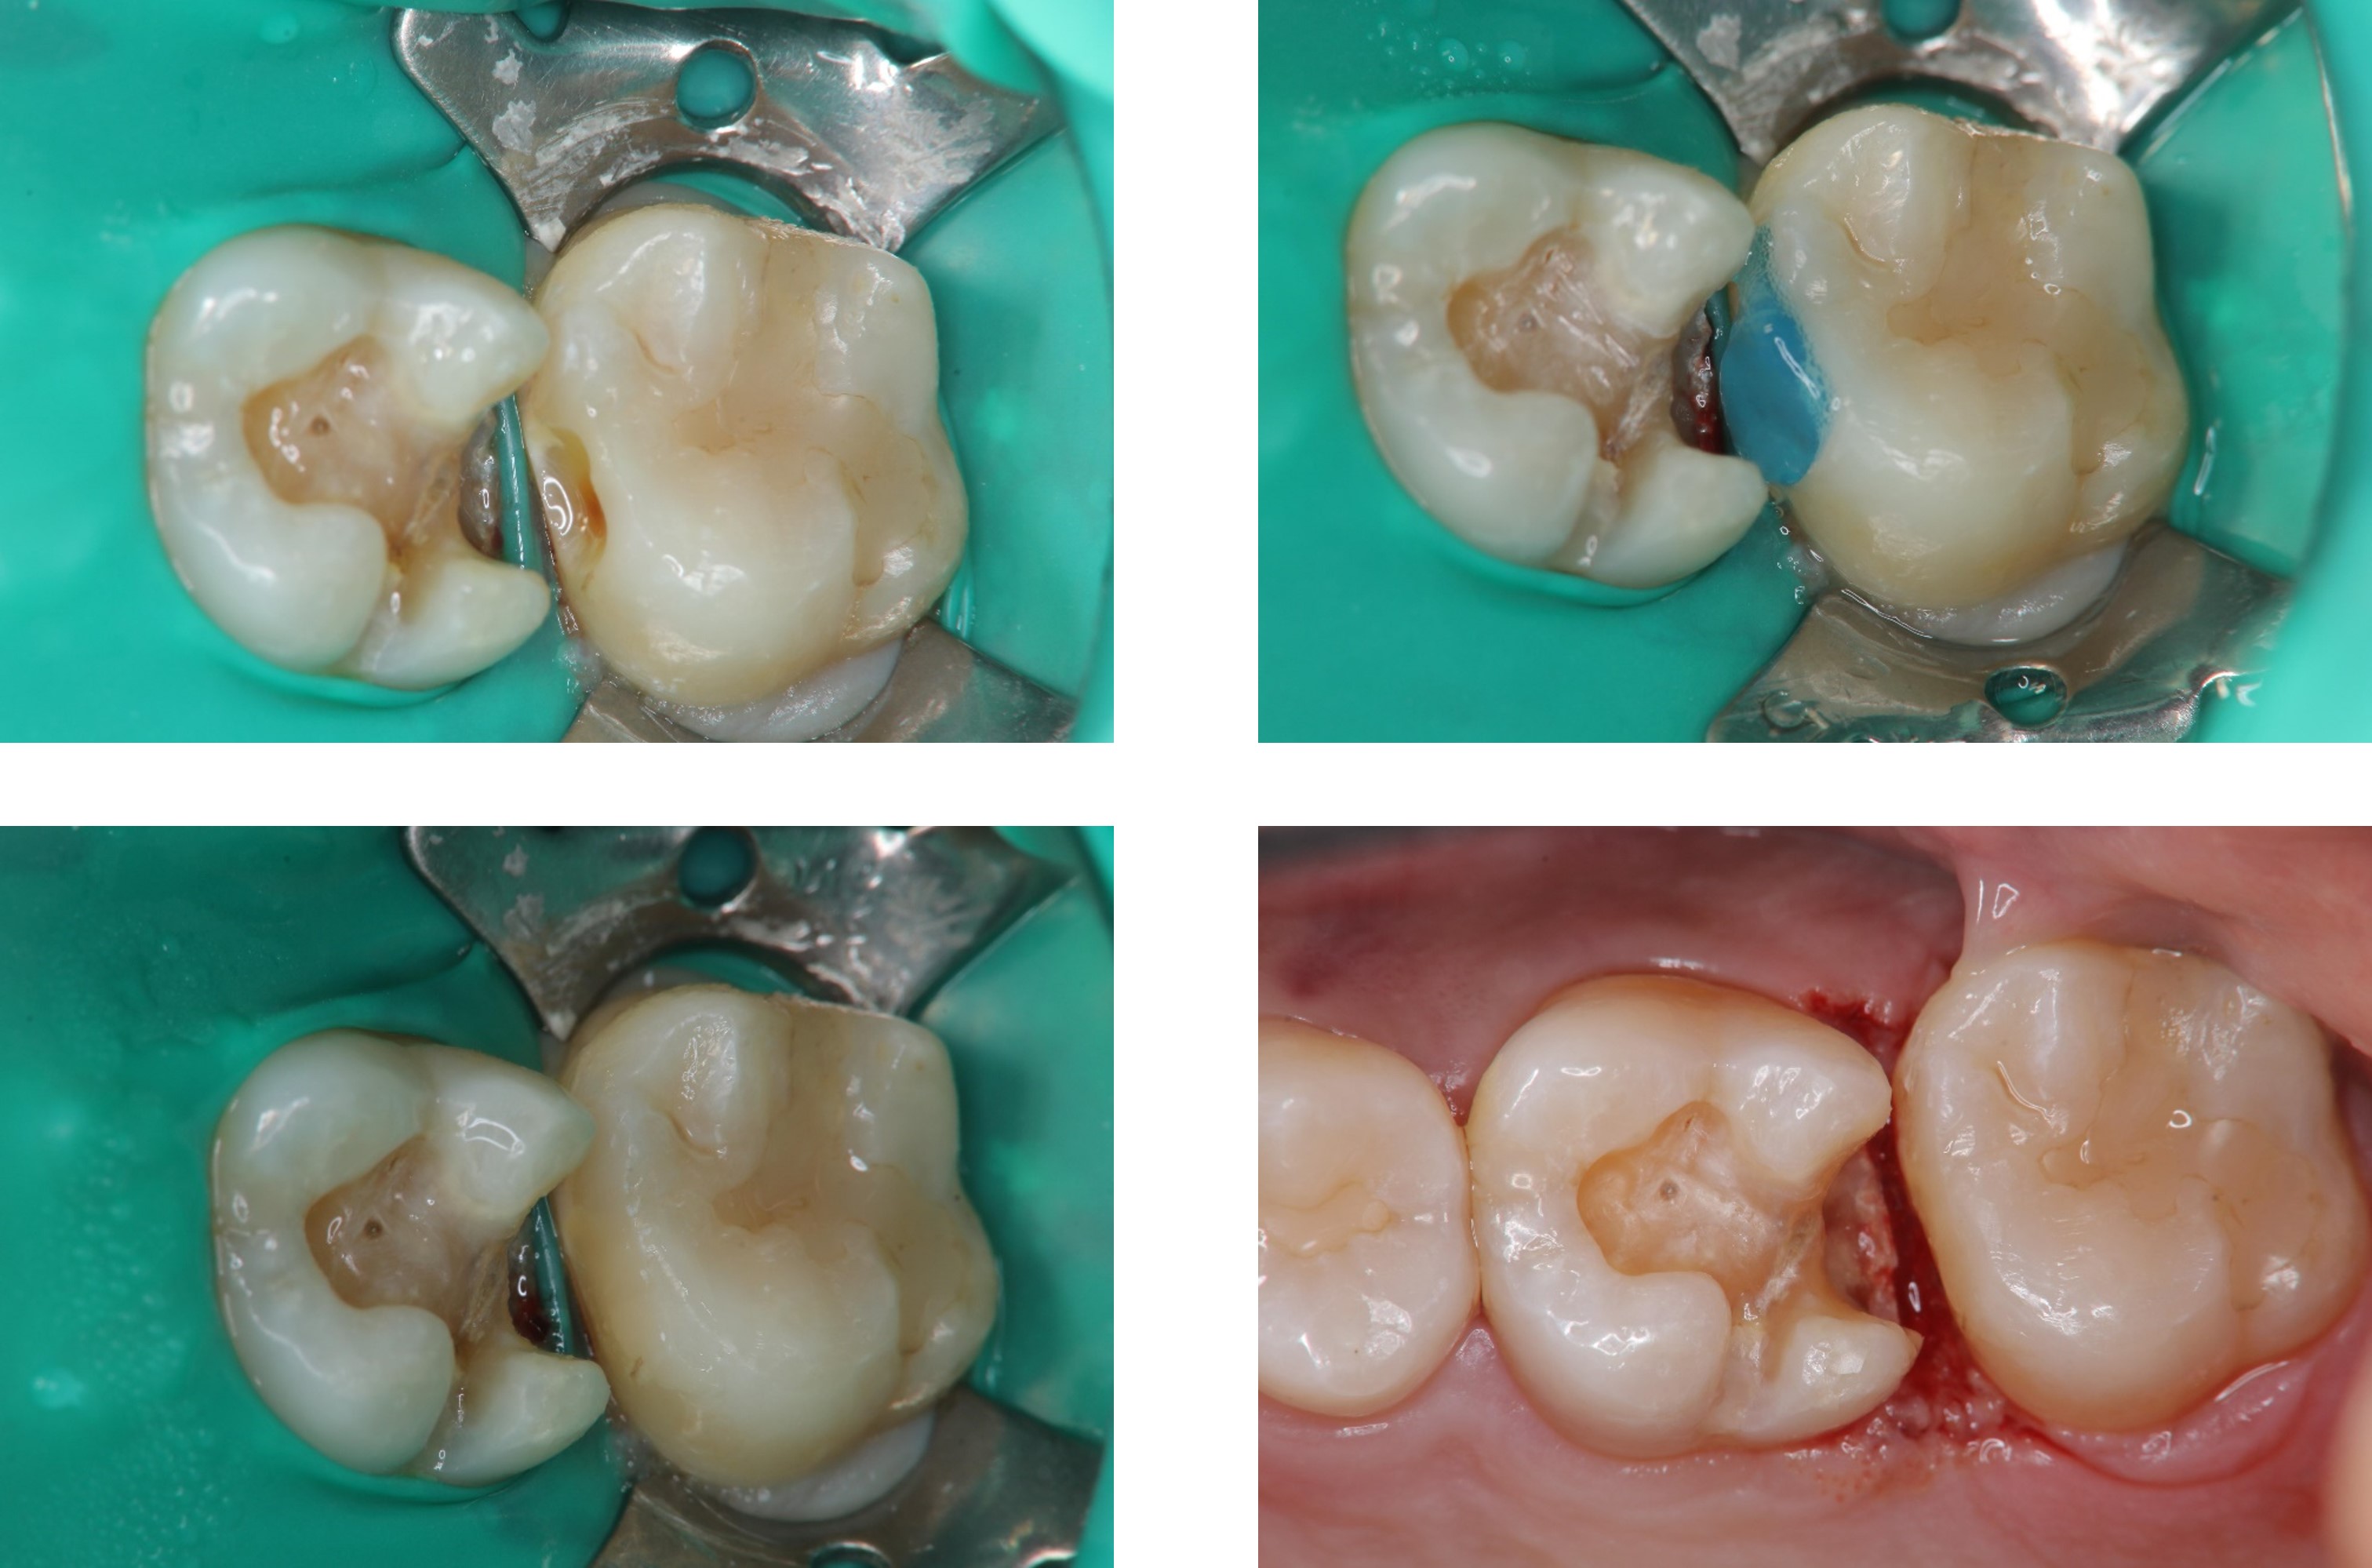

崁體製備,雷射牙齦修整